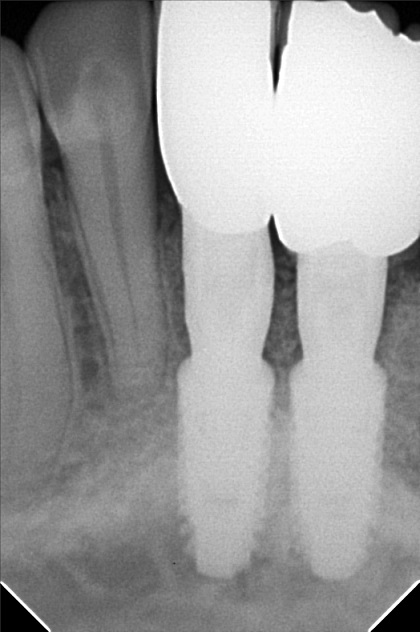

Edit Record Check our patient data records. Add patient information Patient Info Profile picture Last Name First Name Middle Name Birthdate Age Street Barangay City Country Zip Code Contact number Email Procedure 01/30/21 ICF - check up Feb 8,2021 - Implant 11/03/22- OP/OZONE/PAD feb,20,2021- removal of suture march 31,2021- LC 11 & 21 07/31/21 repair 41 zirconia resto 36CAOH/46 CAOH/43/34 OP June 4,2022 - OP / Xray 05/13/23- OP(Moderate); xray; ozone Oct 1 2023 op with air polisher noticed gum recession Removal of fiber splint on 42/43 05/07/24 Air polisher Xray OP 06/15/24 connective tissue graft harvested side: upper right quadrant w/ suture- monofilament absorbable 4/0 donor site: implant #41/32 buccal and lingual combination of monofilament absorbable 4/0 and nylon 6/0 non absorbable 06/22/24 check up 06/29/24 suture removal File raposa_donna_kelly_3.jpg File 2 raposa_donna_kelly_2.jpg File 3 raposa_donna_kelly_1.jpg File 4 donna_kelly.jpg File 5 june_42022.jpg File 6 raposa_donna.jpg File 7 raposa_donna_02.jpg File 8 img_2831.jpg File 9 File 10 File 11 File 12 File 13 File 14 File 15 File 16 File 17 File 18 File 19 File 20 Retain Record Retain Record Yes No Save Your Changes